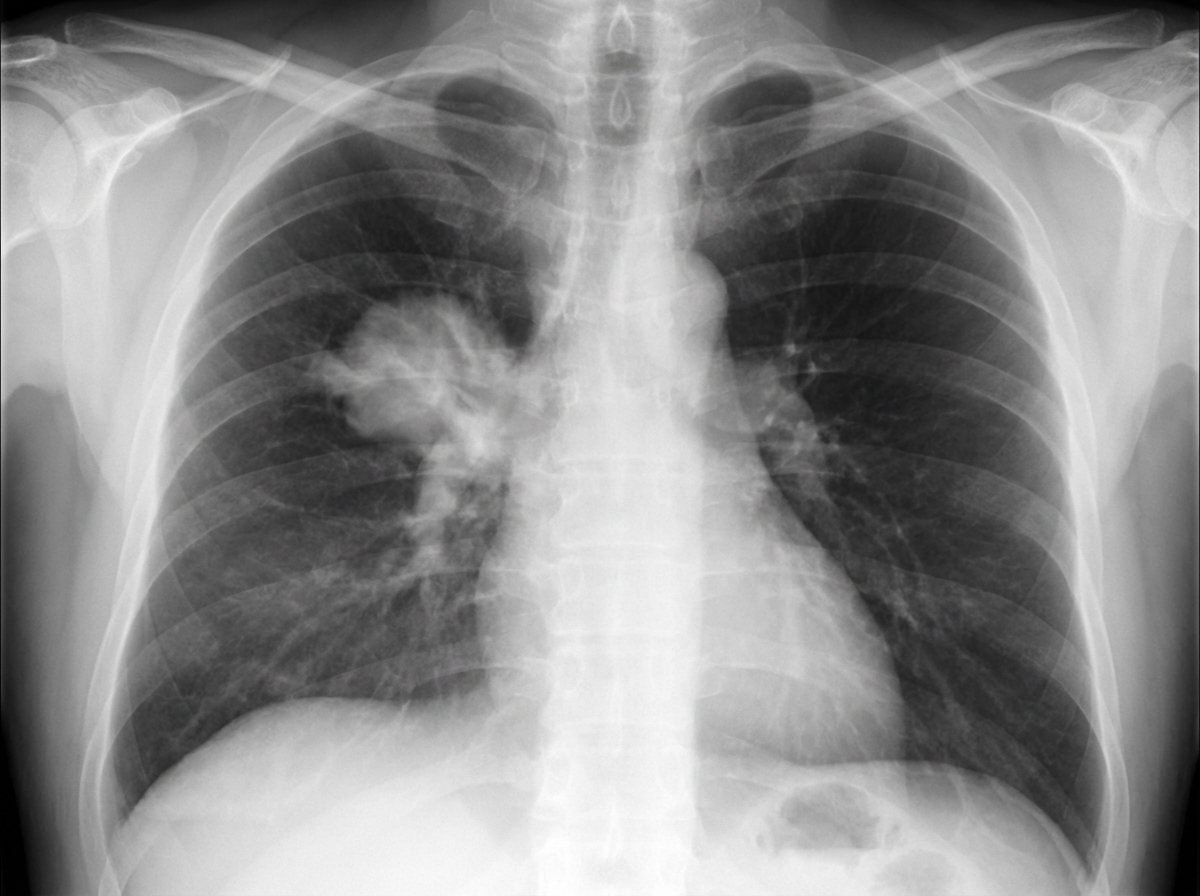

A 71-year-old woman comes to the physician because of a 4-month history of worsening cough and a 4.5-kg (10-lb) weight loss. She has smoked one pack of cigarettes daily for 35 years. Physical examination shows wheezing over the right lung fields. Laboratory studies show a serum calcium concentration of 12.5 mg/dL. X-rays of the chest are shown. Which of the following is the most likely diagnosis?